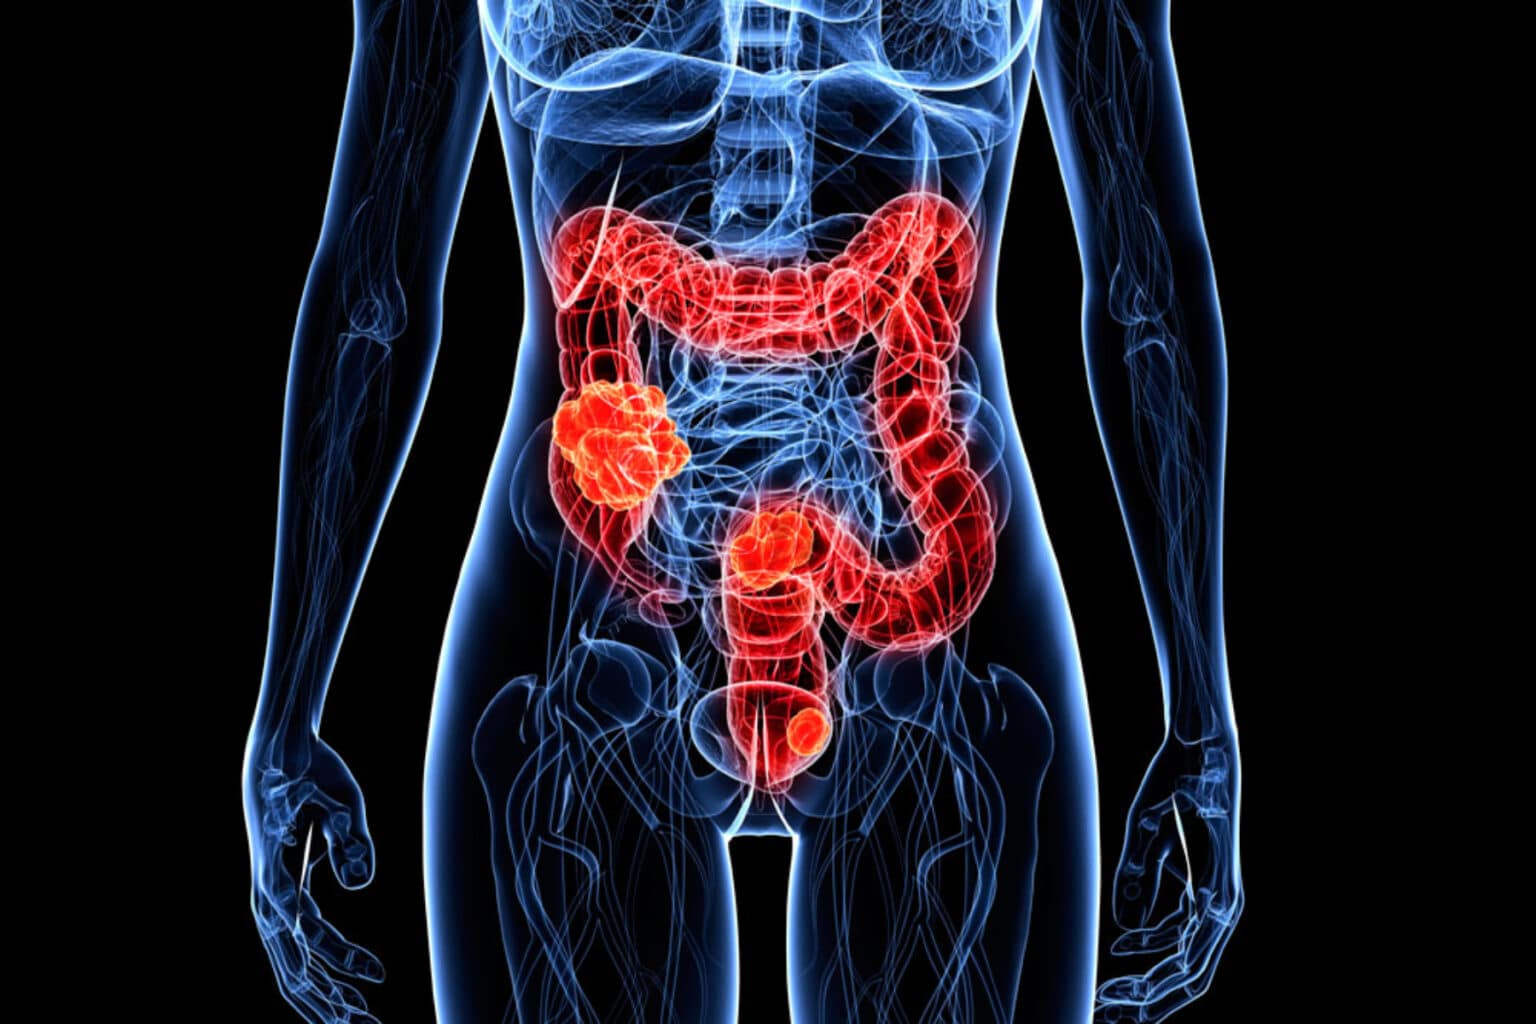

Καρκίνος του παχέος εντέρου